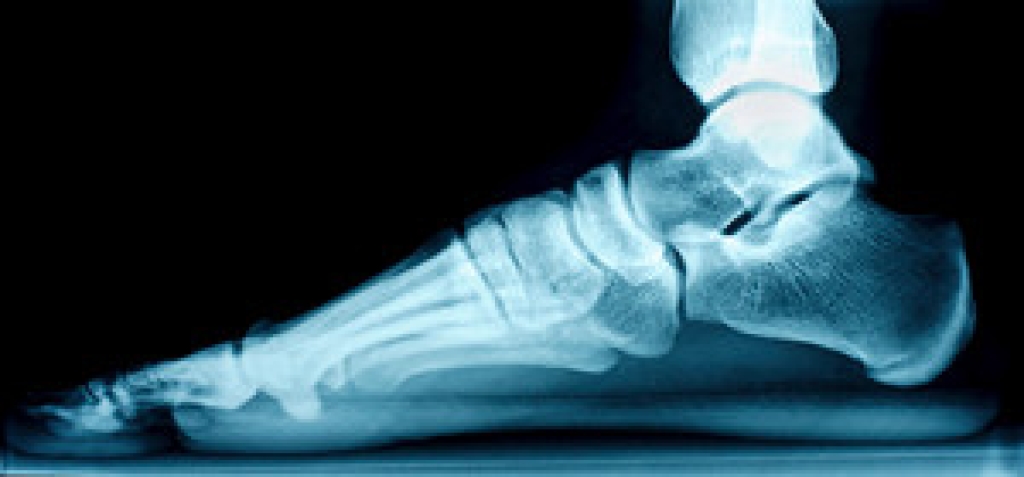

Plantar fasciitis is a common foot ailment characterized by inflammation of the plantar fascia, a thick band of tissue that connects the heel bone to the toes. The condition typically results from repetitive strain or excessive stress on the feet, causing tiny tears in the ligament. Individuals with plantar fasciitis often experience a stabbing pain near the heel, especially with the first steps in the morning. This discomfort may gradually subside during the day, only to resurface after prolonged periods of standing or intense physical activity. The pain tends to be more pronounced after sitting for an extended duration and can impact daily activities, affecting the overall quality of life. Understanding the definition and recognizing the symptoms of plantar fasciitis is essential for timely intervention and management. Plantar fasciitis can cause severe pain and discomfort. If you have developed this condition, it is strongly suggested that you are under the care of a podiatrist who can guide you toward the correct treatment method.

Plantar fasciitis is the inflammation of the thick band of tissue that runs along the bottom of your foot, known as the plantar fascia, and causes mild to severe heel pain.